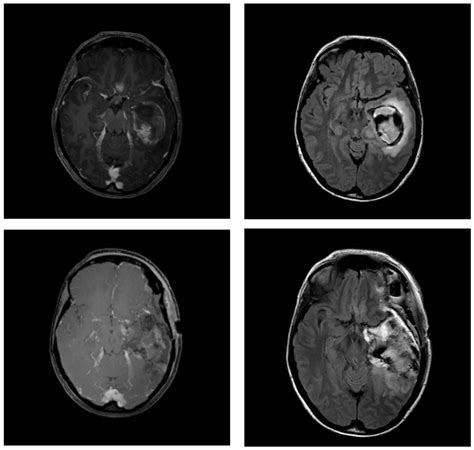

The journey toward a formal diagnosis usually begins with a neurological examination followed by advanced imaging. Physicians rely on several diagnostic tools to map the tumor’s size, location, and relationship to vital brain structures. Magnetic Resonance Imaging (MRI) with contrast remains the gold standard for visualizing these growths. In many cases, specialized sequences such as spectroscopy or perfusion imaging are used to differentiate between tumor tissue and postoperative changes.

• high grade glioma MRI